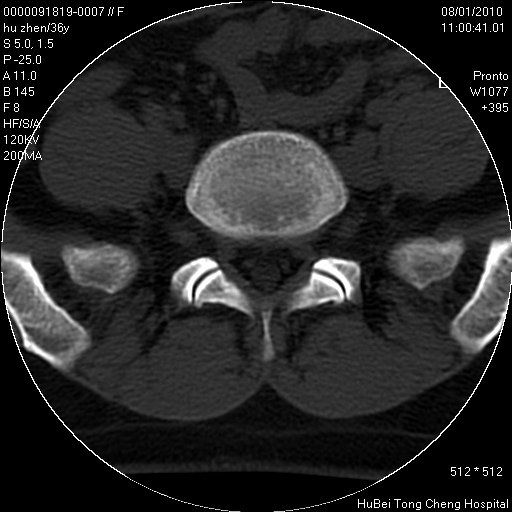

患者 女,36岁。右侧腰腿痛半月余。腰骶椎mr平扫偶然发现骶椎异常信号。

临床诊断:1)腰椎间盘突出症。2)骶椎肿瘤性病变?

骶椎ct平扫(层厚、层距均为5mm),图像如下:

考虑s1骨纤维异常增殖症。

骨良性病变、成骨细胞瘤

考虑s1骨纤